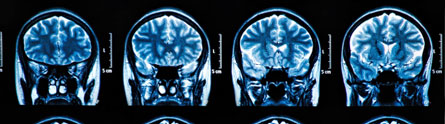

Researchers at The University of Nottingham are using sophisticated MRI technology to provide a fascinating insight into the brain mechanisms involved in the human sense of touch.

The three-year study, funded with £690,000 from the Medical Research Council, will reveal the cortical processing of the sense of touch at an unprecedented level of resolution. The researchers predict their project will provide new insights into the sense of touch and, in particular, why nerve pathways are altered in patients suffering from some types of neurological disorders.

The Nottingham academics will use a powerful 7 Tesla MRI scanner to look at somatosensory functionality across the six different layers of cortical grey matter in the region responsible for touch and how these could be impaired. They will be linking up with experts at Gothenburg University who have pioneered a technique which can produce the perception of very localized touch in response to electrical stimulation of an individual touch nerve fibre which will allow them to examine the activity of the brain in healthy subjects in order to develop a detailed picture of which areas of the brain ‘light up.’